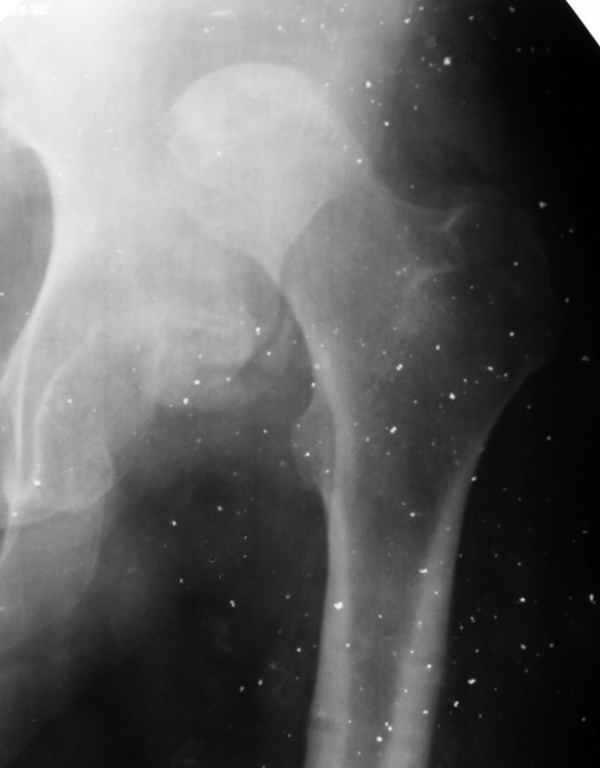

Здравствуйте. К нам поступил мальчик 15 лет с застарелым 7-месячным вывихом бедра из области. Травма мотоциклетная, при поступлении в больницу по месту жительства диагностирован перелом диафиза бедра и не распознан вывих бедра с этой же стороны.

Бедро было синтезировано пластиной и успешно срослось. Как поступить сейчас с вывихом? По КТ видны интерпонированные отломки, впечатление что это фрагменты головки бедра. Поделитесь, пожалуста, опытом. Спасибо.

What happened with femoral head?AVN?Plain x ray uncertain.

Фрагменты в проекции вертлужной впадины кажутся задненижним сектором голоки бедра